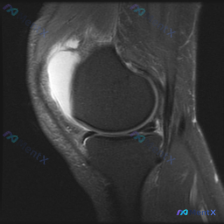

看到这份读片请求,整理了完整分析思路和大家分享。 病例基本情况 本次仅提供单张膝关节矢状位T2加权MRI图像,用户关注核心问题为「半月板异常」,无其他临床病史、体征信息。 影像学核心发现 1. 异常表现 - 髌上囊区可见明显均匀T2高信号,提示大量膝关节积液,这是图像最突出的异常; - 其他结构评估...